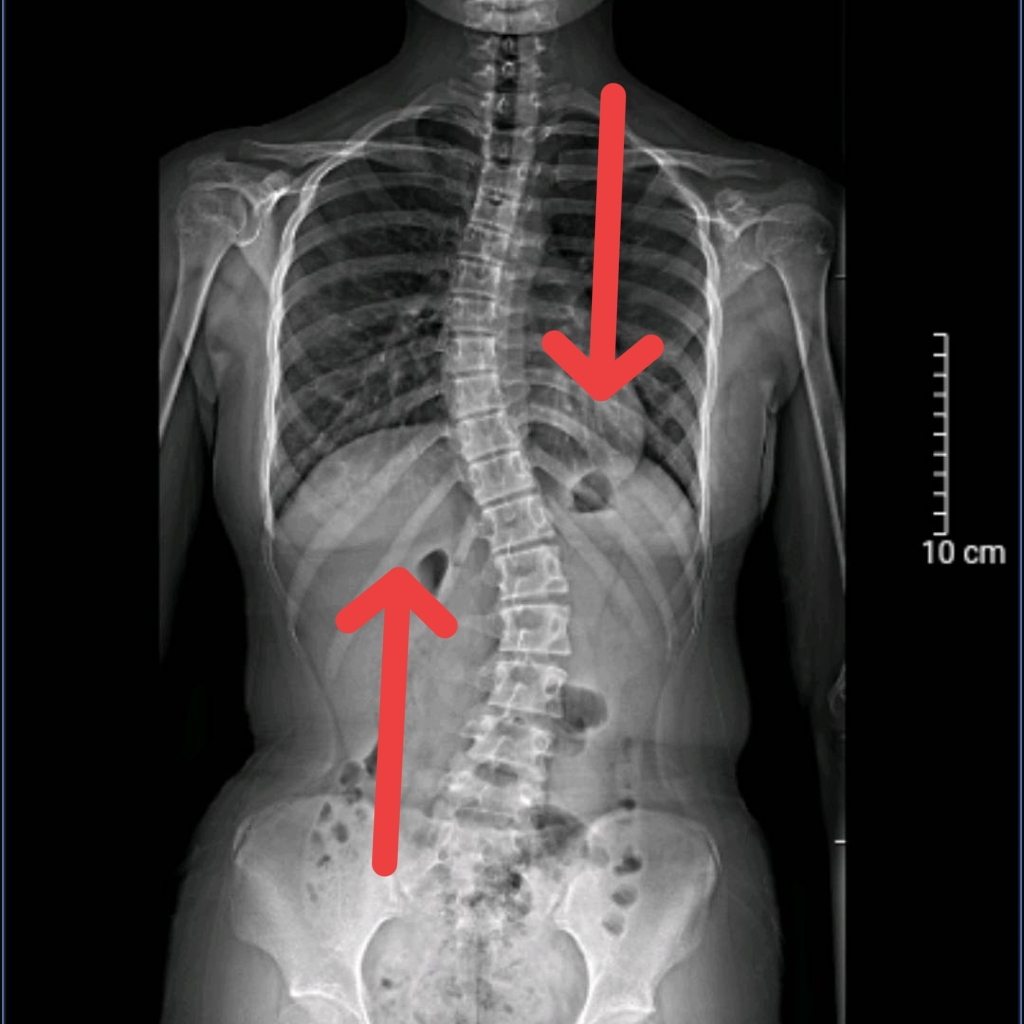

如果您发现,家里的孩子习惯身体倾向一侧?两侧肩膀一高一低?驼背背部不对称?左右腰线不同?那可要注意啦!很可能就是脊柱侧弯!

脊柱侧弯的危害

①外观体态畸形、身体发育受阻

④心肺脏器功能障碍、极重度侧弯将危及生命

1.Cobb角<10°时,定期观察,自身加强锻炼

2.10°~20°时,运动干预加康复治疗

3.>20°~45°时,选择支具治疗配合康复治疗

4.>45°时,考虑手术治疗。